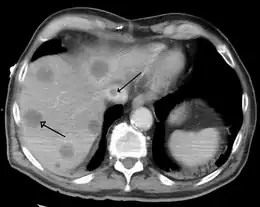

Syndrome de Budd-Chiari secondaire à un cancer, les flèches indiquent un caillot dans la veine cave inférieure et une métastase dans le foie.

Le Scanner avec injection permet de visualiser la compression ou l'occlusion des veines sus-hépatiques, de même l'IRM avec injection. Ils mettent aussi en évidence les défects perfusionnels hépatiques[3].